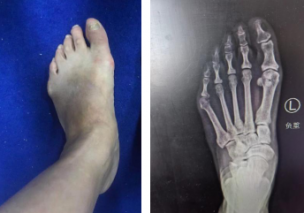

踇外翻俗称“大脚骨”,是一种常见的踇趾向足的外侧过度倾斜、第一跖骨内收的前足畸形,女性居多。

踇外翻的四个阶段

1、严重足部畸形,影响美观

如何治疗踇外翻?

sararz足踝团队采用4毫米低频超声骨刀微创截骨,切口很小无需缝合;低频超声骨刀锋利、精准、自带注水降温,能更好地保护骨骼血运,使得截骨处更快愈合,手术基本无血渗出,完美修整踇外翻,术后第二天就能下地行走。